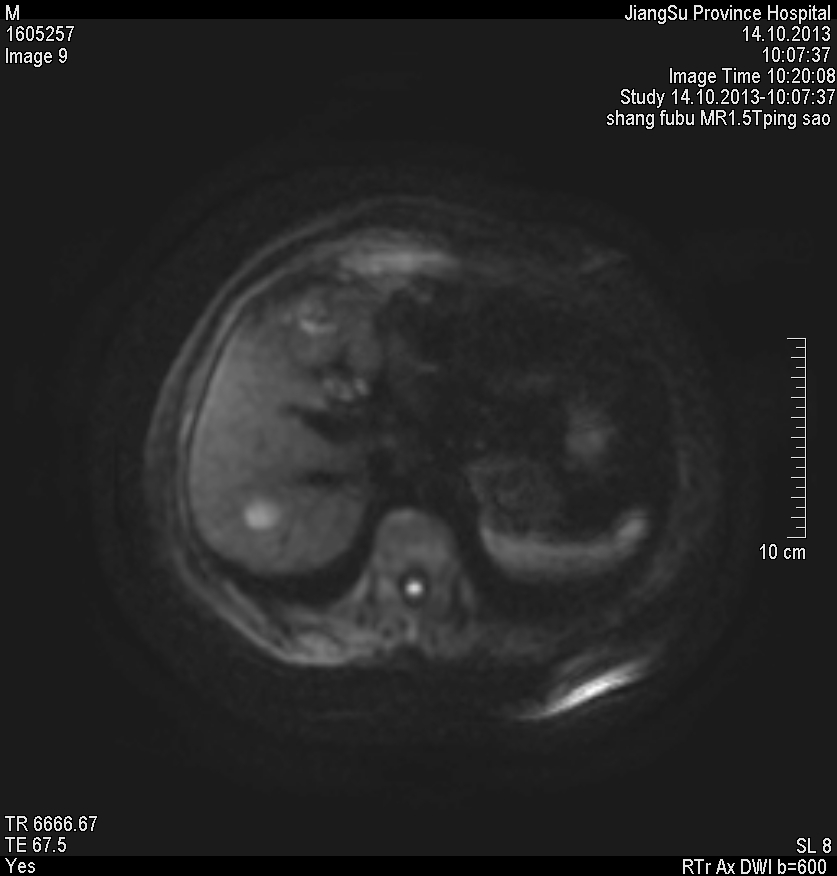

水成像高信号,同反相位均呈低信号,动脉早期轻度强化,其余时期强化不明显

肝脏右叶内有一明显圆形肿块,增强CT肝实质期不强化,MRI水成像高信号,其他呈低信号,动脉早期轻度强化。